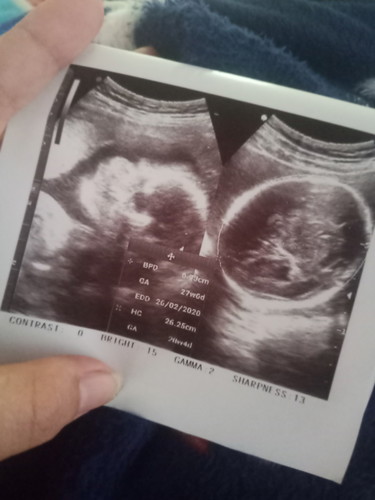

เเม่ๆๆคนไหนเคยมีประสบการน้องมีน้ำในสมองบ้างคะอายุครรห์27+3 มีน้ำในสมองประมาณ11.1 m แม่เคลียดมากเลยคะ??